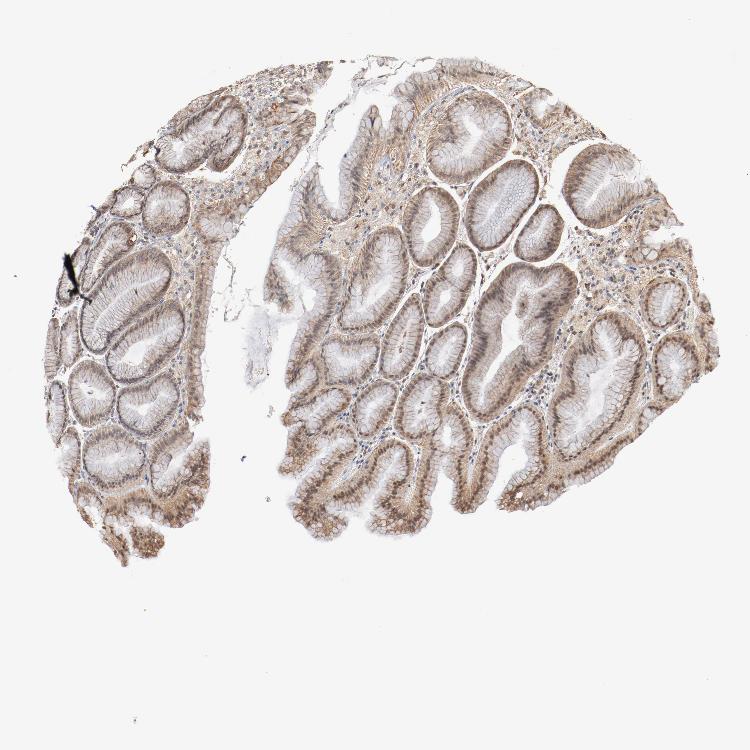

STOMACH 2 - Antibody stainingi

Antibody staining in the annotated cell types in the current human tissue is reported as not detected, low, medium, or high, based on conventional immunohistochemistry profiling in selected tissues. This score is based on the combination of the staining intensity and fraction of stained cells.

Each image is clickable and will lead to virtual microscopy that enables deeper exploration of all samples and also displays staining intensity scores, fraction scores and subcellular localization as well as patient and tissue information for each sample.

Antibody HPA003725

Glandular cells Low